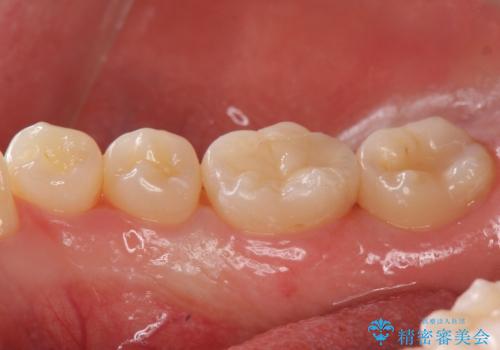

見た目にはわかりにくい奥歯の虫歯 セラミックインレーでの治療

- 検査の結果虫歯が確認された患者様です。

見た目ではわかりにくい虫歯ですが、レントゲン画像でははっきりと写っていました。

まだ虫歯の大きさが小さいためインレーでの修復処置を行います。

虫歯が大きくなりきる前に治療を行えたため、歯の削る量を抑えることができました。

精度の良い詰め物は今後の虫歯リスクを抑えることにもつながります。